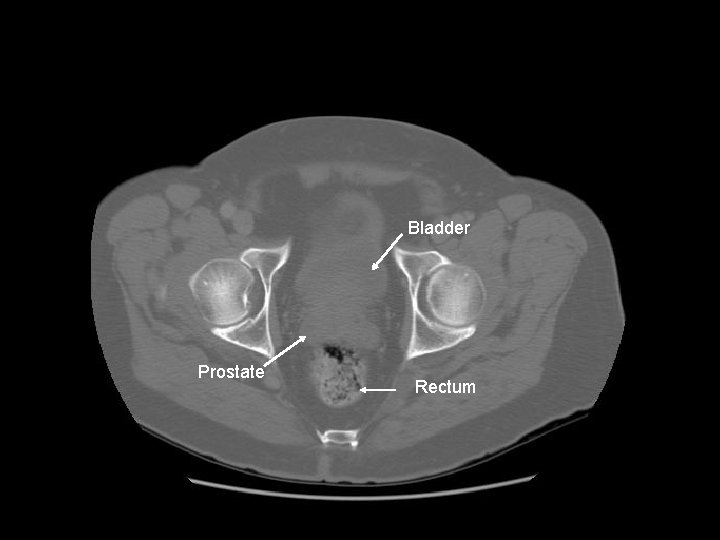

Bladder Prostate Rectum